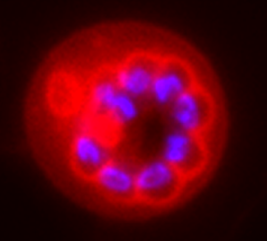

Bioassay facility